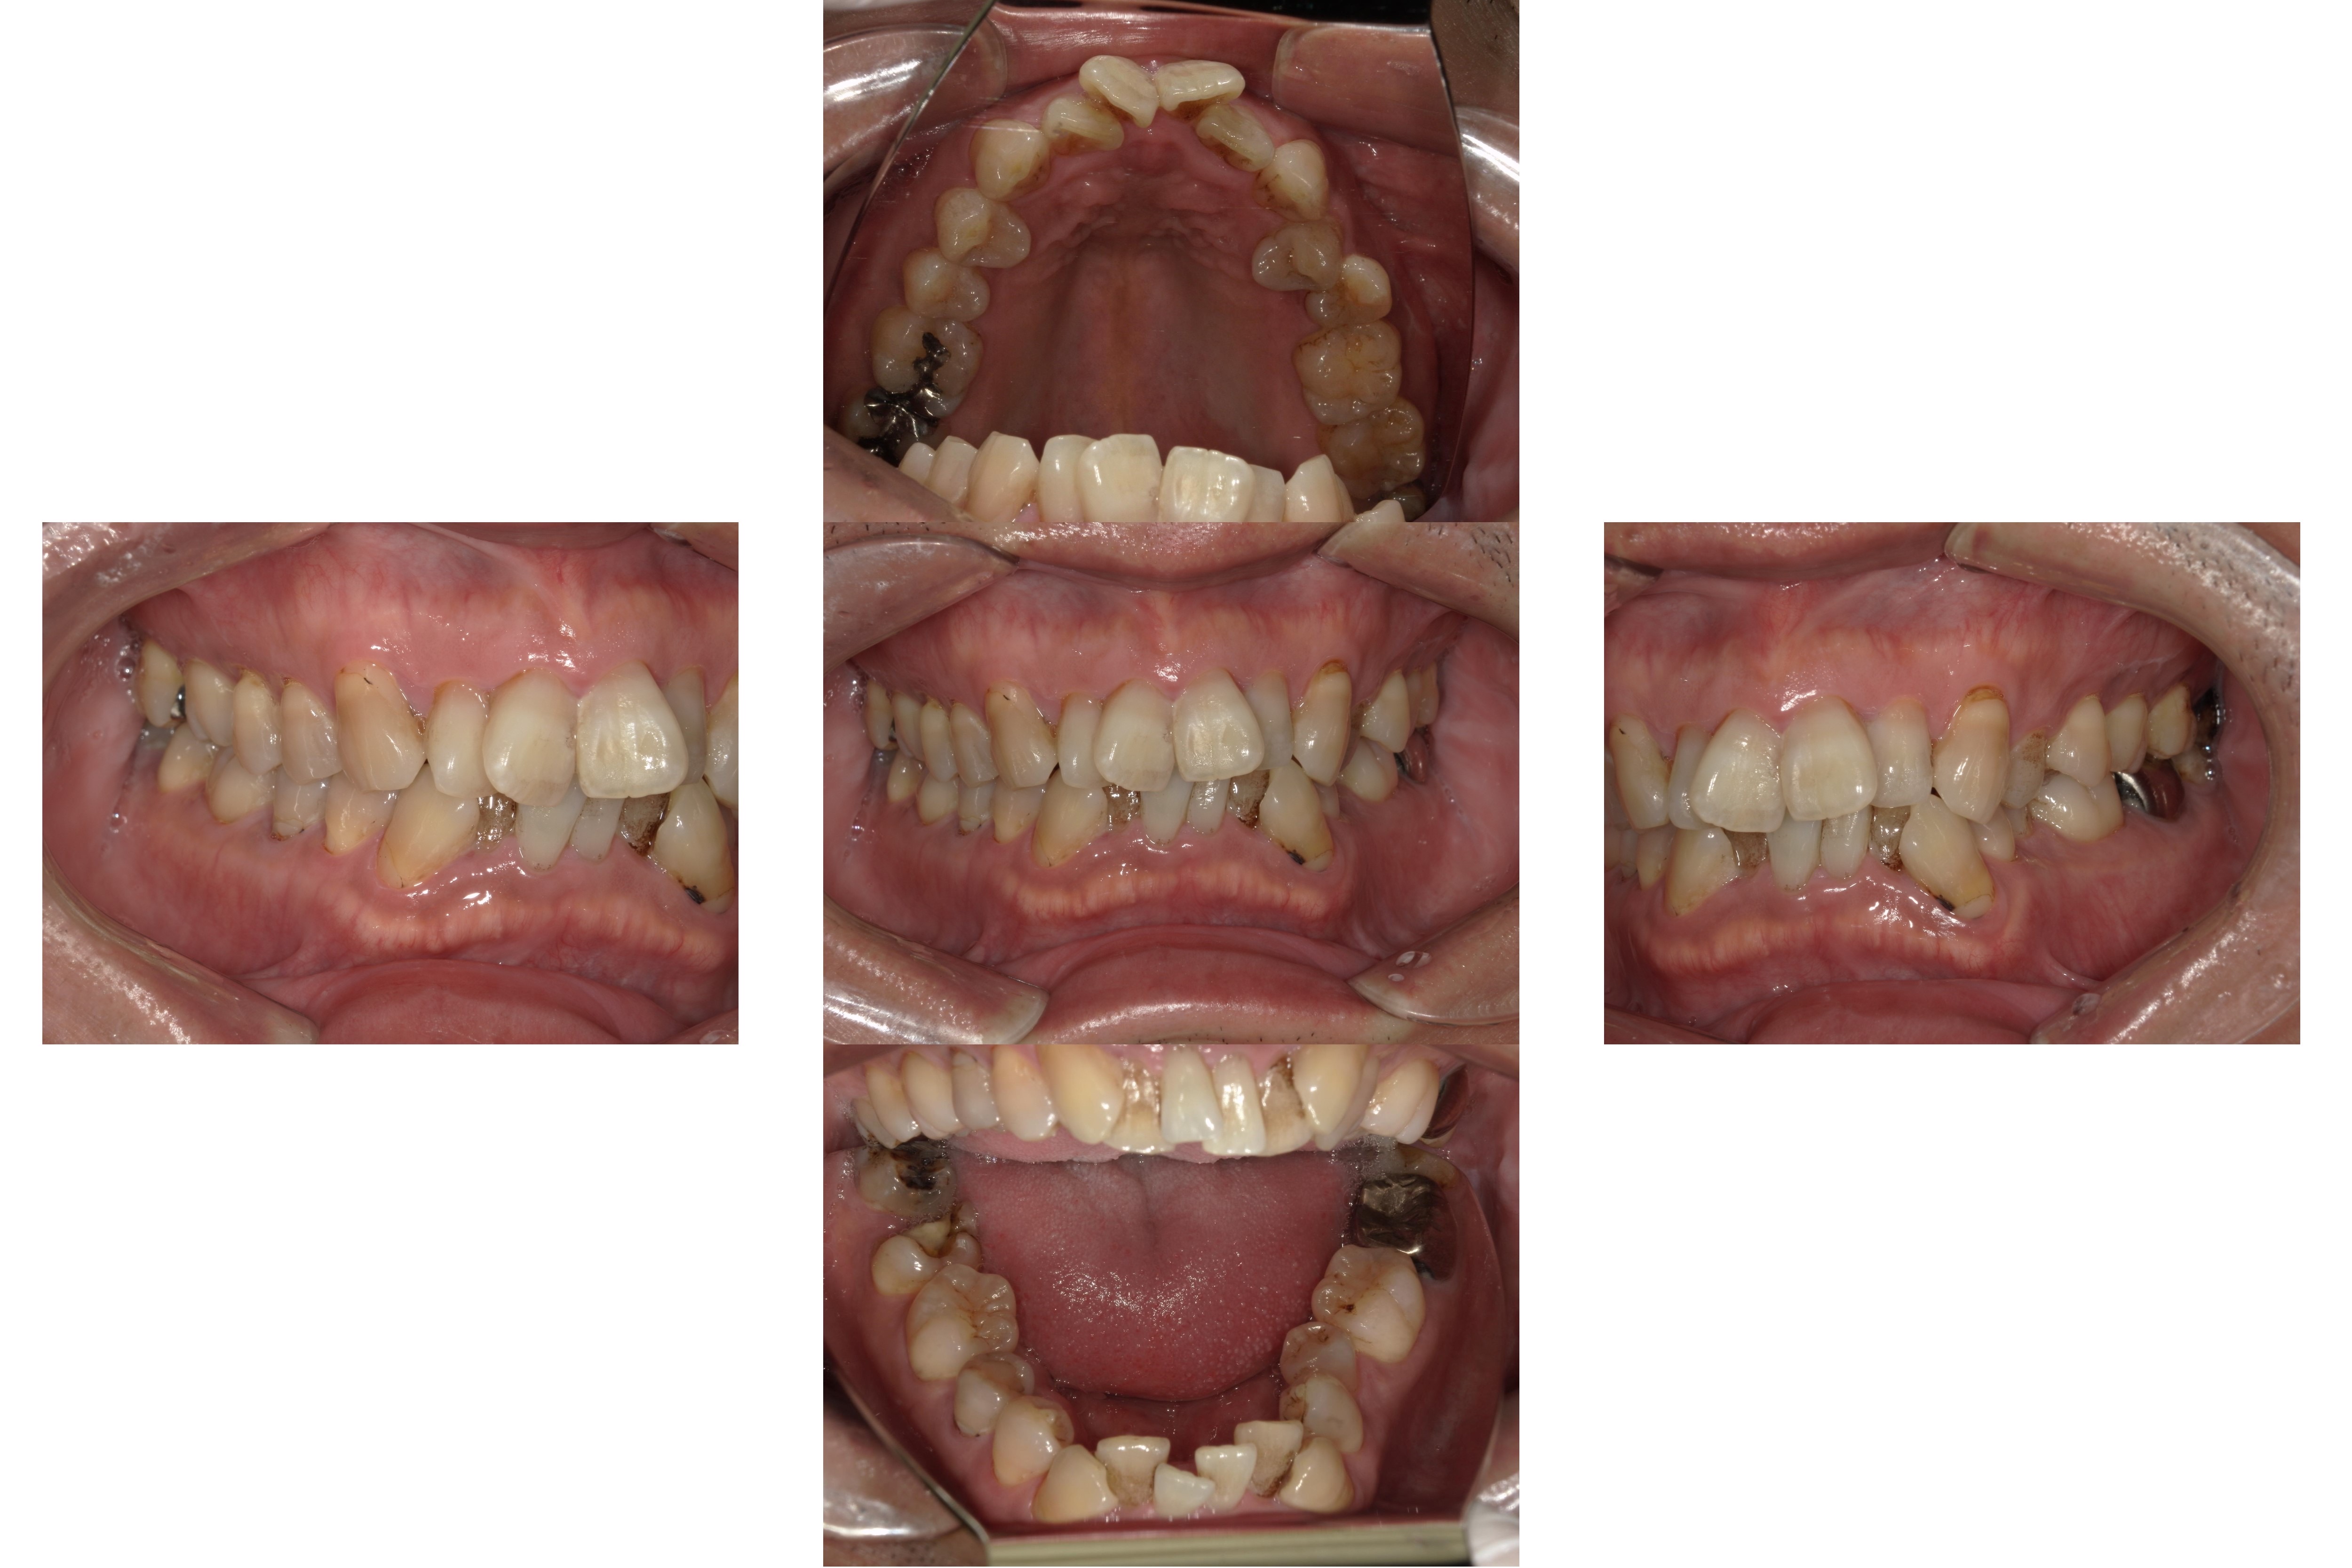

親知らずは、一般的に20歳前後に生えてくる最後の歯で、歯列の一番奥に位置します。親知らずがまっすぐ生えないケースも多く、顎のスペースが足りずに横向きや斜めに生えてくることも少なくありません。

横向きに生えた親知らずは、隣の歯に悪影響を与えたり、歯ぐきを圧迫して炎症を起こしたりする可能性があるため、抜歯が検討されることが一般的です。

横向きに生えた親知らずは、抜歯を推奨されることが多いです。そもそも、親知らずは歯列の最奥に生えるため、歯ブラシが届きにくく汚れが残りやすいです。虫歯や歯周病のリスクが高いため、抜歯を検討することが少なくありません。

さらに、横向きに生えている場合、歯冠が露出していないことが多いです。歯茎や顎の骨に一部が埋まっていることが非常に多く、この場合は汚れが蓄積されやすいです。

また、横向きの親知らずは、周囲の歯を押し広げたり、歯並びに悪影響を与えたりする可能性もあります。そのため、痛みや炎症がなくても、将来的なリスクを避けるために、横向きの親知らずは抜歯することが多いのです。

親知らずが横向きに生えていると、前歯や隣の歯を圧迫して、歯並びが悪化する可能性があります。歯並びに影響が出なかったとしても、隣接する歯の根元が吸収されるリスクがあります。将来的に隣接する歯の寿命が短くなるリスクもあるでしょう。

親知らずが横向きに生えていると、歯ブラシが届きにくく、清掃が不十分になりやすいです。そのため、親知らず自体や周囲の歯に歯垢がたまり、虫歯や歯周病のリスクが高くなります。

特に、親知らずとその手前の歯の間には汚れが溜まりやすく、細菌の温床となって慢性的な炎症を引き起こすこともあります。虫歯や歯周病が重症化すれば、治療にも時間がかかり、その他の健康な歯にも悪影響が及ぶ可能性があります。